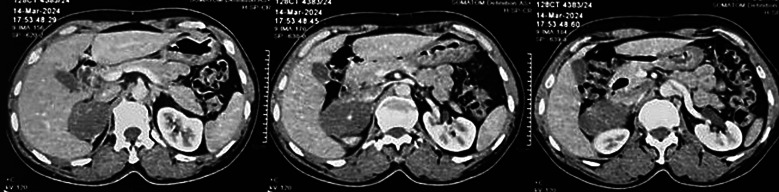

Case presentation: A male patient in his early 60s with a history of hypertension presented with an adrenal incidentaloma. Imaging revealed a well-defined, hypodense right adrenal mass (35 HU) with calcifications and an enlarged aortocaval lymph node, raising suspicion for carcinoma. Biochemical analysis showed a non-functional adrenal tumour. Intraoperatively, the mass appeared benign, but the lymph node deposit suggested malignancy. Histopathological examination confirmed right adrenal ganglioneuroma with metastatic deposits in the aortocaval lymph nodes. The patient recovered well postoperatively, with normal serum cortisol levels and no signs of recurrence at 6-month follow-up.